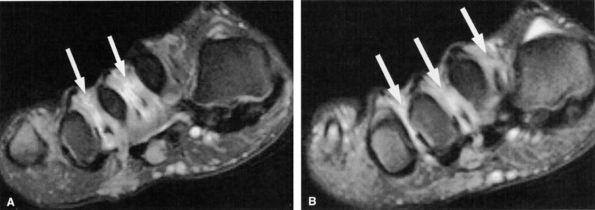

An oval or dumbbell-shaped mass of intermediate to low signal on both T1- and T2-weighted MR images located in the intermetatarsal space. The mass frequently extends into the plantar subcutaneous fat and may be associated with intermetatarsal bursitis (Fig. 6.59).

T1-weighted images are optimal for detecting the neuroma since they provide good contrast between the lesion and the adjacent fat.

T2-weighted images serve to confirm the diagnosis as well as to exclude other diagnostic possibilities, such as true neuromas, intermetatarsal bursitis, ganglion cysts, and synovial cysts.178,193,194,195

The lesion is centered in the neurovascular bundle, within the intermetatarsal space and on the plantar side of the transverse metatarsal ligament.

The lesion is well demarcated.

The signal intensity of the lesion is similar to that of skeletal muscle on TI-weighted images and less than that of fat on T2-weighted images (see Fig. 6.59).

FIGURE 6.59 ● Third intermetatarsal Morton's neuroma. Dumbbell mass (arrows) of intermediate to low signal on both T1-weighted (A) and T2-weighted (B) images extends from the intermetatarsal space to the plantar aspect of the foot. (C) The mass enhances after gadolinium administration.